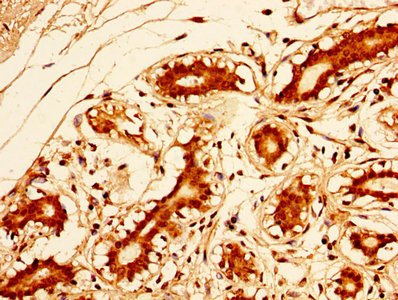

IHC image of CSB-PA16539A0Rb diluted at 1:500 and staining in paraffin-embedded human lung cancer performed on a Leica BondTM system. After dewaxing and hydration, antigen retrieval was mediated by high pressure in a citrate buffer (pH 6.0). Section was blocked with 10% normal goat serum 30min at RT. Then primary antibody (1% BSA) was incubated at 4°C overnight. The primary is detected by a biotinylated secondary antibody and visualized using an HRP conjugated SP system.